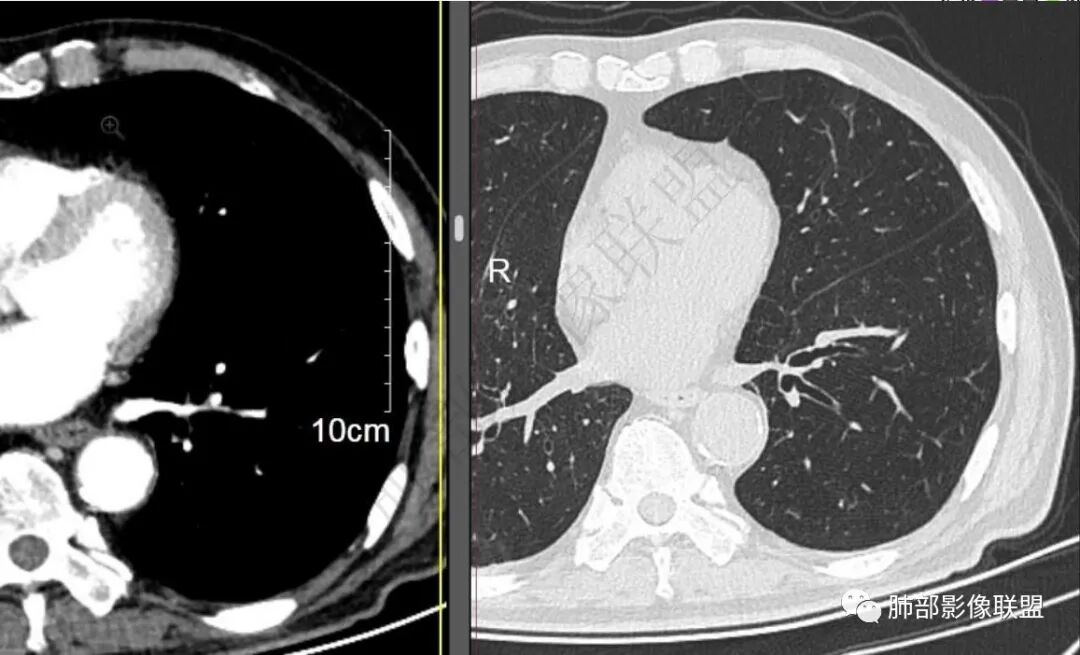

再1个多月后病灶继续增大,较明显不均匀强化,肺门一侧见低密度区。病灶边缘相对不清,可见毛刺。